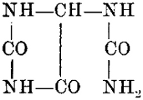

The intimate connection which recent research has shown to exist between the arrangement of the constituent parts of an organic molecule and physiological action, has been considered at some length in a separate chapter.

| 25. | The Influence of Carbonyl Groups, | 39 |